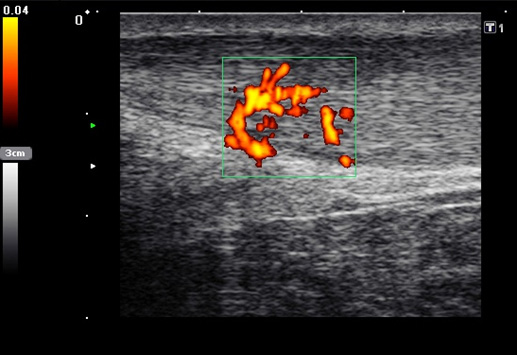

Die Farb-Doppler-Sonographie wurde 2001 erstmalig von Ohberg und Alfredson in Umea in Schweden bei schmerzhaften Achillessehnen eingesetzt 17. Bei 21 symptomatischen Sehnen konnten intratendionös mit Hilfe der Farb-Doppler-Sonographie pathologische Blutgefäße als Neovaskularisation nachgewiesen werden, die sich bei Achilles-gesunden Kontrollgruppe nicht fanden. Wenig später berichtete dieselbe Arbeitsgruppe über die erfolgreiche Farb-Doppler-kontrollierte Sklerosierung der Neogefäße mit Polidocanol 18.

2001 verglich Richards et al. die Power-Doppler-Sonographie bei symptomatischen Achillessehnenbeschwerden mit der Magnetresonanztomographie 19. Die Neogefäße in der Power-Doppler-Sonographie korrelierten mit Signalveränderungen in den T2-gewichteten MRT-Sequenzen. Aufgrund der guten Reproduzierbarkeit und Verfügbarkeit hat sich die Power-Doppler-Sonographie inzwischen bei der Darstellung der kleinen Neogefäße mit ihrem langsamen Blutfluss etabliert 202122. Die Neogefäße dringen von ventral in die Achillessehne ein. Typischerweise sind diese Neogefäße erst ab einem Sehnendurchmesser von >6,5mm nachweisbar. Bei erfolgreich behandelter Achillestendinopathie kann nach einem Jahr ein Rückgang der Anzahl der Neogefäße in der Power-Doppler-Sonographie, eine Durchmesserreduktion sowie eine Normalisierung der MRT-Signalalteration beobachtet werden 23. In einer Fallstudie konnte ein Abfall des Neovaskularisationsvolumens bei einem Patienten mit mid-portion Achillestendinopathie von 463mm3 auf 117mm3 belegt werden 24. Dies ging mit einer Verbesserung des Schmerzes in der visuellen Analogskala (von 8 auf 0) und des VISA-Scores (von 2 auf 92) einher.

634 asymptomatische Marathonläufer wurden mit der hochauflösenden Power-Doppler-Sonographie (12MHz) anlässlich von 23 Marathonveranstaltungen und 6 und 12 Monate im Anschluss untersucht 25. Mit einer odds ratio von 6.9 (p<0,001) konnte eine Neovaskularisation bei asymptomatischen Läufern die Entwicklung einer midportion Achillestendinopathie anzeigen. Eine positive Vorgeschichte für Achillessehnenbeschwerden hatte eine odds ratio von 3,8 und stellt damit ebenfalls einen ernst zu nehmenden Risikofaktor für weitere Beschwerden dar.